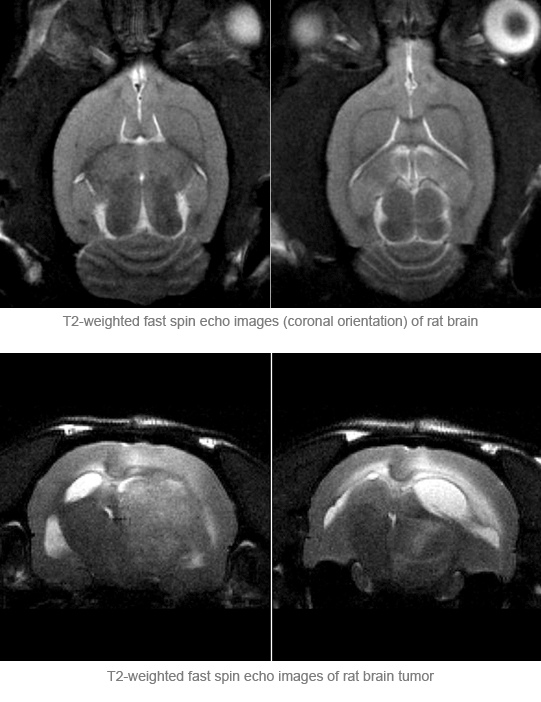

Advanced Pharmaceutical Applications